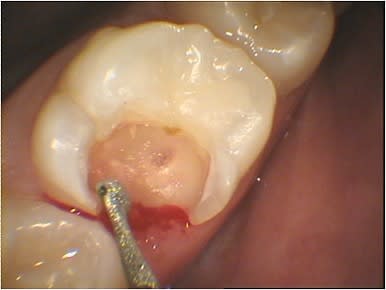

Par comparaison, quelques photos de coiffage pulpaire au CO²

Après hémostase, stérilisation et vitrification, la carbonisation est facilement éliminée aux US et si besoin avec du Negatol (un antiseptique). Cette carbonisation peut être évitée et son importance dépend du matériau ou du tissu traité, elle peut aussi servir à la détection de dentine infiltrée. Les protéines sont déstructurées à 60°, l’effet thermique en mode superpulse ou chopérisé est bactéricide et la puissance crête peut atteindre 200W mais son absorption reste très limitée (0.1mm) donc sans danger pour la pulpe.